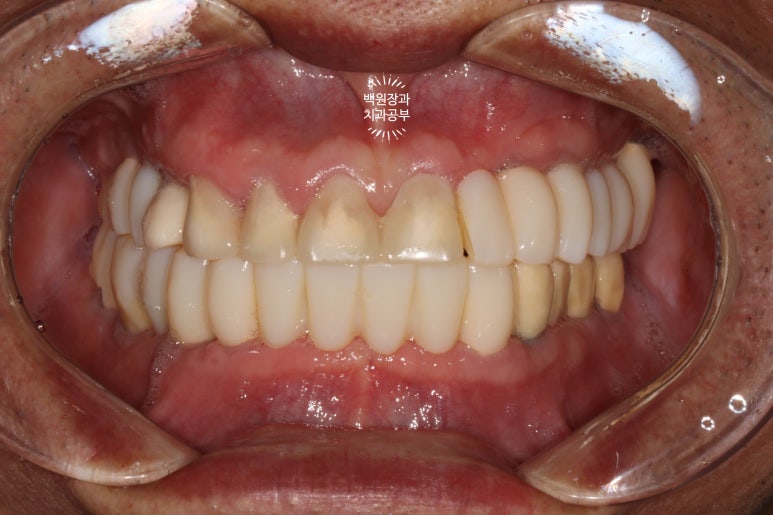

대망의 최종 보철물 완성 후!!!

최종 보철물로 완전히 교체 후 구강내 사진입니다.

순차적으로 포스팅을 읽으신 분들은... 첫 모습을 이미 까먹으셨을텐데요...

처음 내원시 구강내 사진을 생각하신다면!!! 정말 놀라운 변화가 아닐 수 없죠...

제자리를 잃어버렸던 치아들이 모두 가지런하게 되었고,

치아 사이의 벌어진 틈은 지르코니아 보철물을 이용해서 모두 깔끔하게 채워드렸으며,

치아의 색상 또한 60대 남자 환자분의 피부색에 맞추어 어울리게 그리고 화사하게 바꿔드린 상태입니다.

금속색 하나 비춰보이는 것 없이 완벽하네요....

역시 저희 치과의 보철과 전문의 원장님의 장인정신은 혀를 내두를만 합니다.